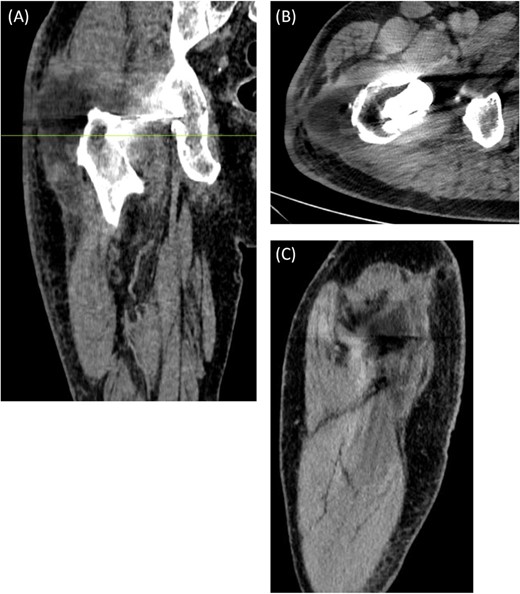

An ultrasound scan of his hip and thigh was performed which showed a large 10.1 cm × 4.3 cm, complex collection with mixed solid/cystic components. This was associated with a tract extending from the skin surface and a deeper fluid collection that tracked along the posterolateral right femoral shaft (Fig. 3). A subsequent CT femur with contrast reported a large collection adjacent to the greater trochanter with no evidence of fistulous communication with the joint. A separate locule of fluid 2.5 cm in length was seen superior to this and communicated with the main collection. There was no sign of prosthetic loosening or radiological evidence of osteomyelitis (Fig. 4).

(A) Coronal, (B) Axial (C) Sagittal CT scan of right femur with contrast. The axial image is taken at the level marked on the coronal image. There is a large 8.3 cm × 4.5 cm × 4.5 cm collection seen adjacent to the greater trochanter with no evidence of fistulous communication with the joint. A separate locule of fluid 2.5 cm in size was seen superior to this and communicated with the main collection. There was no sign of prosthetic loosening or radiological evidence of osteomyelitis.